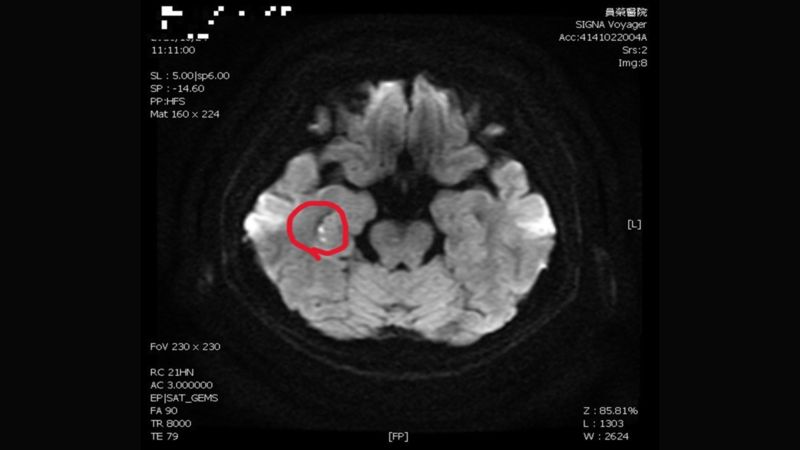

▲陳彥秀醫師表示,患者接受腦波檢查是正常;但核磁共振,看到她右側海馬迴出現一點亮亮的影像。(圖/員榮醫院提供)

陳彥秀醫師表示,患者接受腦波檢查是正常;但核磁共振,看到她右側海馬迴出現一點亮亮的影像。海馬迴與記憶功能密切相關,證實她「短暫性全面失憶」狀況,是因為情緒過於激動,中風所造成。